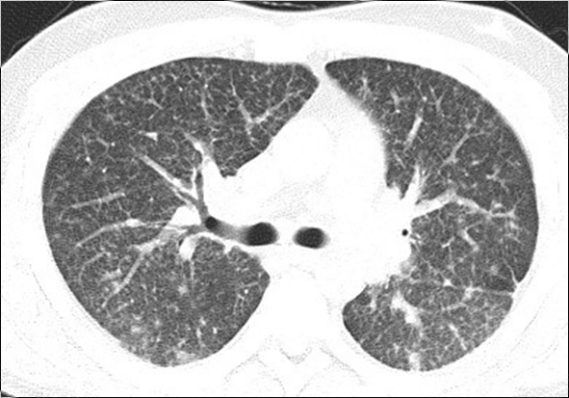

影像学资料:

2017年3月

2017年7月

2018年2月

2018年3月